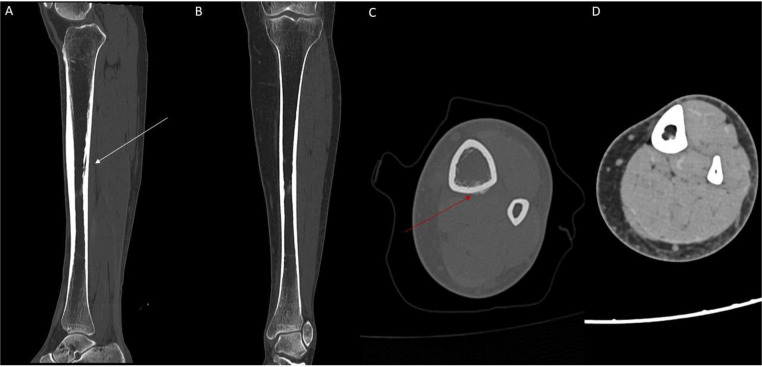

Due to the presence of bone edema, CT was performed to rule out a stress fractures (Fig. 4).

Fig. 4.

(A) sagittal CT showing linear osteolytic image with adjacent sclerosis (white arrow) (B) coronal CT (C) axial CT of the distal one-third of the tibial diaphysis showing periosteal reaction (red arrow). (D) No bone or soft tissue mass lesions were noted.